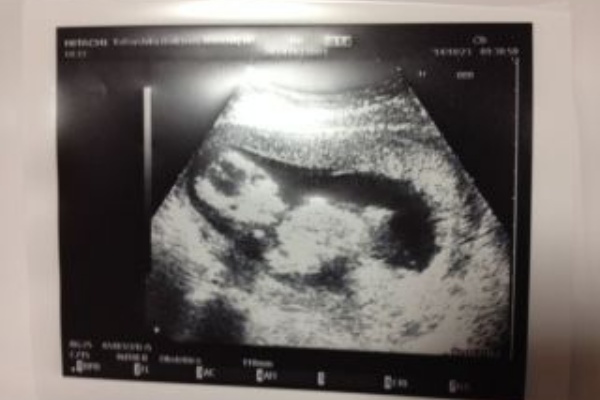

妊娠14週 エコー カルボナーラ 結婚生活 育児記録 18年21歳で結婚 19年妊娠 出産 1才児ママ